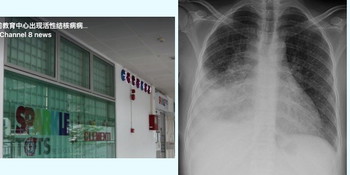

Tuberculosis (TB) is a disease which primarily affects the lungs, and is caused by the bacteria Mycobacterium tuberculosis. TB is spread when a person with active TB coughs or sneezes, and expels the germs into the air. It usually requires prolonged and close contact with someone with active TB, to get infected with TB.

The initial stage or the first infection with the tuberculosis bacteria is called latent TB. Latent TB usually shows no signs or symptoms, and is not contagious. Active TB is characterised by fever, profuse sweating at night, and chronic persistent cough (sometimes with blood). Tuberculosis is known to aggravate in small children, especially in those less than 5, due to their weak immune systems.